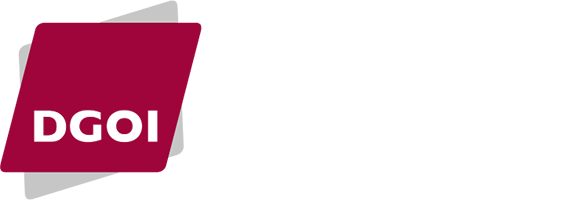

Surgical laser when used as a method of decontamination on different implant surfaces depending on power intensities, bacteria kill rates of up to 99.4% have been attained. The CO2 and Er:YAG lasers are recommended, since it appears that they do not exert a negative impact on the implant surface.23 The Er:YAG laser generates the least amount of heat in the bone tissue surrounding the implant16. Another type of laser with a low thermal effect on the bone and implant surface is the Er, Cr, YSGG (Waterlase), which represents an improvement over the technical properties of the Er:YAG and which surely has a bright future in this field.23 (FIG 1,2,3)